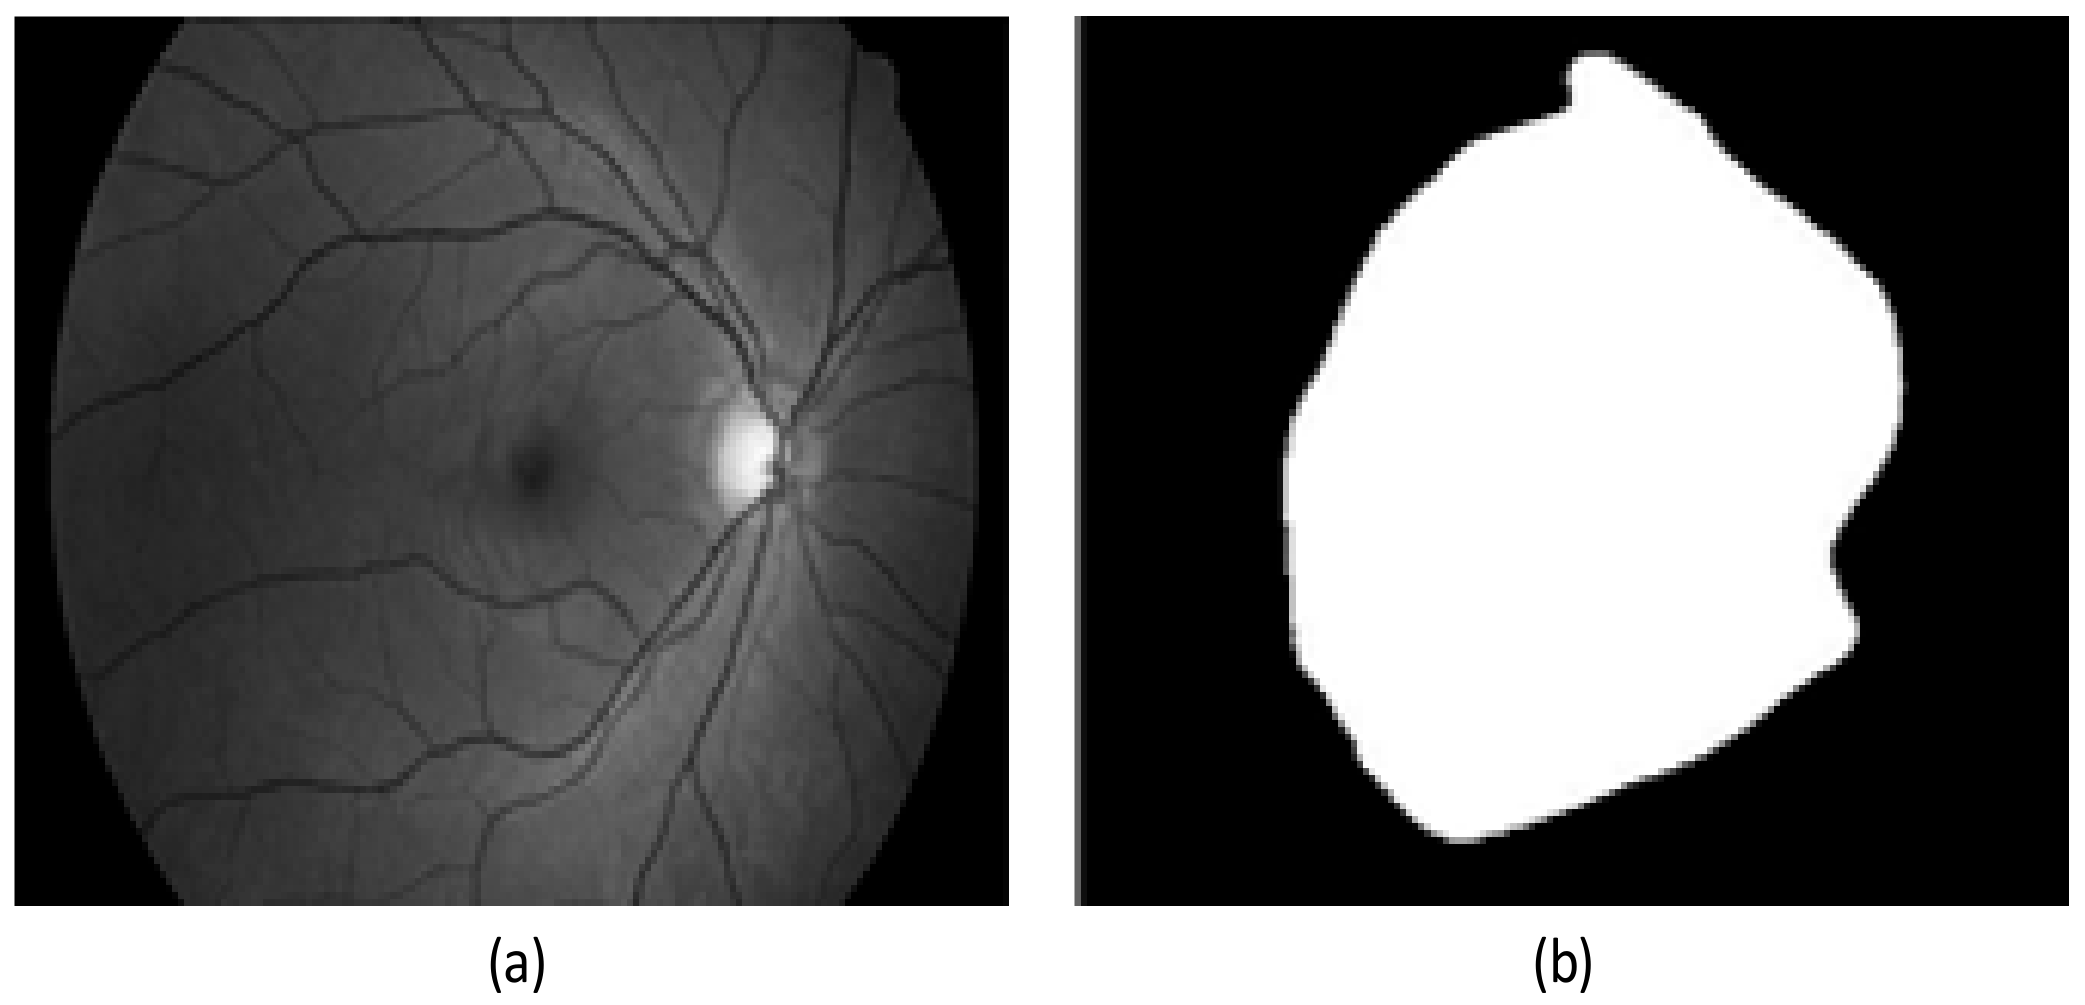

2.2. Preprocessing Based on Adaptive Thresholding